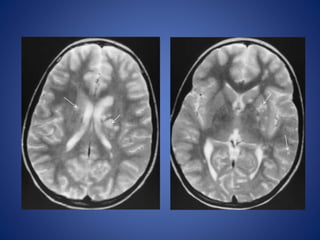

FLAIR DWI

7 Months male…………………………………………….

FLAIR DWI 7 Monthsmale…………………………………………….